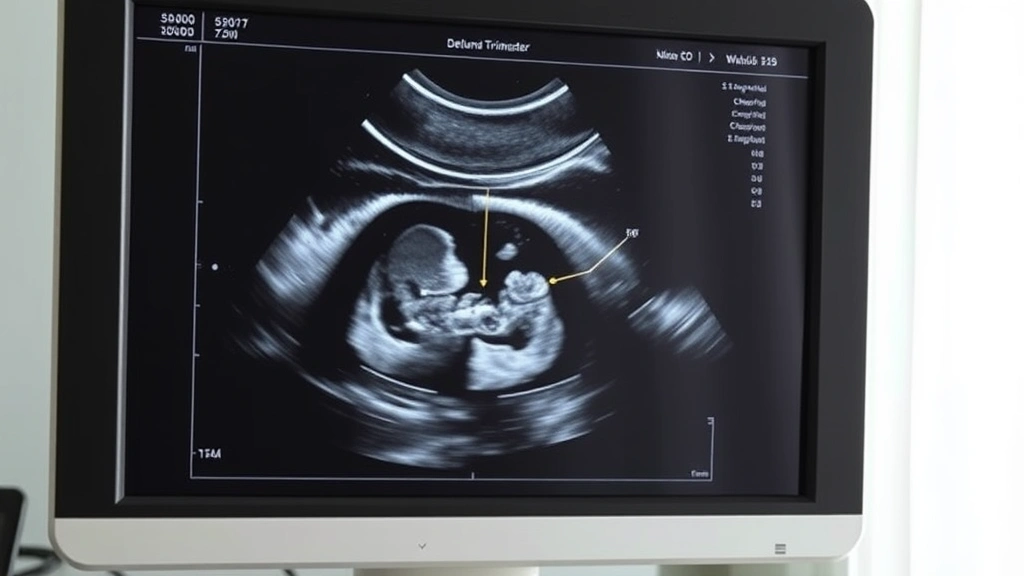

The sweet spot for gender determination arrives during the second trimester, particularly between weeks 18-22. This is when most healthcare providers perform the anatomy scan, a detailed ultrasound that examines your baby’s development and can accurately determine gender in most cases. During this appointment, the technician will look at the angle of the genital tubercle and surrounding structures to identify whether you’re having a boy or girl.

At this stage, accuracy rates reach approximately 99% for boys and 95% for girls, though the angle of the baby and image quality can affect results. This is the ideal time to plan your baby shower and begin decorating your nursery with confidence.

Modern ultrasound technology uses sound waves to create images of your baby inside the womb. Understanding how technicians identify gender helps you appreciate the science behind this exciting discovery.

The anatomy scan, performed during weeks 18-22, is the standard ultrasound where gender is typically revealed. During this appointment, your technician will:

- Apply warm gel to your abdomen to help sound waves travel through tissue

- Use a transducer (handheld device) to emit sound waves at frequencies between 2-18 megahertz

- Capture images of your baby’s organs, limbs, and reproductive structures

- Measure various fetal parameters to ensure healthy development

- Identify gender by examining genital anatomy

Technicians identify gender by looking for specific anatomical features. For male babies, the scrotum and penis are visible, and the genital tubercle points upward at an angle of approximately 30 degrees or more from the horizontal plane. For female babies, the genital tubercle is more vertical, pointing downward toward the feet, and the labia majora may be visible as parallel lines.

The accuracy of gender identification depends heavily on the baby’s position during the ultrasound. If your baby is in an awkward position with legs crossed or turned away from the transducer, the technician may not be able to determine gender with certainty.